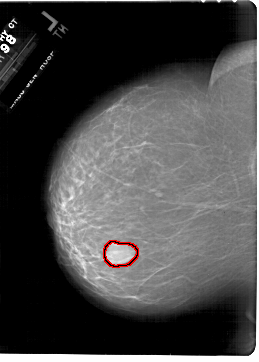

A_1801_1.RIGHT_MLO

RIGHT_CC LINES 6196 PIXELS_PER_LINE 4396 BITS_PER_PIXEL 12 RESOLUTION 43.5 NON_OVERLAY

RIGHT_MLO LINES 6736 PIXELS_PER_LINE 5041 BITS_PER_PIXEL 12 RESOLUTION 43.5 NON_OVERLAY